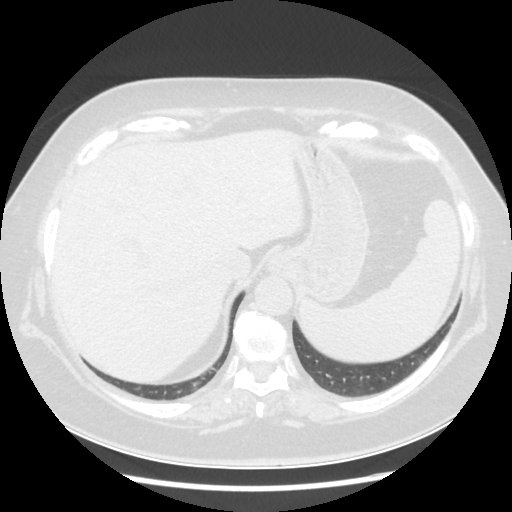

Reconstructed NATIVE CT scan (cycle consistency)

Full window (WL 1023.5, WW 4095 β†’ Low βˆ’1024, High +3071)

Original VENOUS CT scan